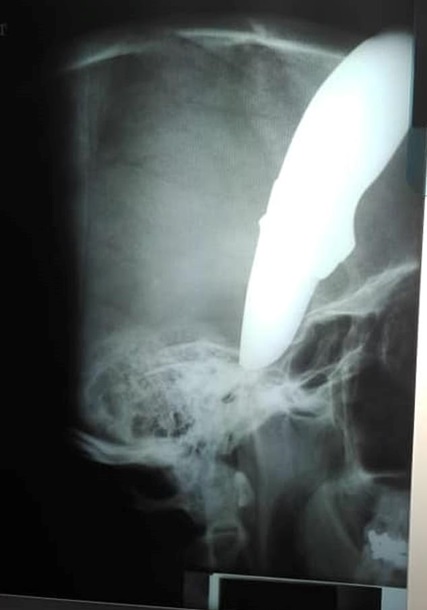

В южноафриканском Кейптауне мужчина Шон Уэйн приехал на велосипеде к врачу с ножом голове. Такими были последствия встречи с ворами. Об этом сообщает Daily Mail.

Лезвие длиной 15 сантиметров погнулось о череп и вошло в лицо, не задев мозг.